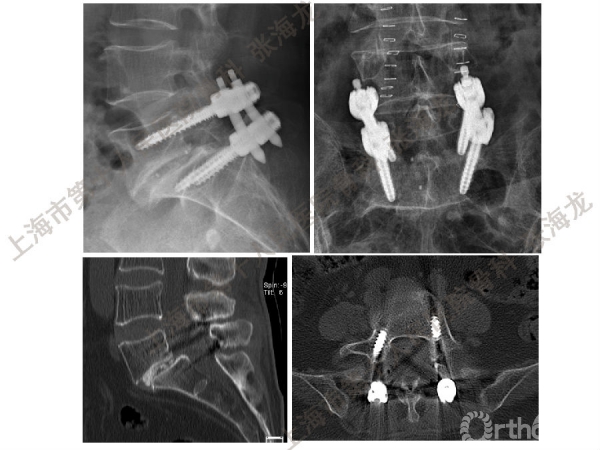

2008年3月至2010年8月,上海市第十人民医院骨科随访49例腰椎滑脱症(峡部裂型和退变型)患者,对比23例微创手术MIS-TLIF和26例开放手术治疗腰椎滑脱症的临床及影像学结果,进行了回顾性研究。

研究发现,Wiltse入路Mis-TLIF更直接的暴露峡部及关节突,对脊柱稳定性的影响较小;彻底松解辅助双重提拉复位Mis-TLIF,对于峡部裂型滑脱有较好的复位效果;对于峡部裂型滑脱,提拉复位在影像学参数上有一定优势;与原位融合相比,ODI.VAS.JOA无明显差异(样本量有限);对于退变性滑脱,单纯撑开椎间隙与原位融合可以获得较好疗效。